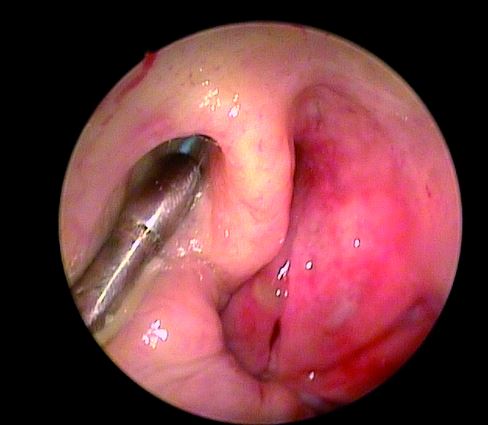

Kateter do trąbki Eustachiusza - TubaVent

System TubaVent to nowatorska, małoinwazyjna i bezpieczna metoda leczenia chronicznych dysfunkcji trąbki Eustachiusza. Kateter balonowy pod kontrolą endoskopu wprowadzany jest do trąbki słuchowej za pomocą specjalnie zaprojektowanego instrumentu. Przy użyciu dedykowanej pompy do części dystalnej kateteru wprowadza się płyn pod ściśle określonym ciśnieniem. Efektem tego zabiegu jest powiększenie światła trąbki słuchowej i przywrócenie jej normalnego, prawidłowego funkcjonowania.

Liczne badania naukowe potwierdzają bardzo wysoką skuteczność i efektywność tej metody. System TubaVentz powodzeniem zastosowano już u ponad 20.000 pacjentów na całym świecie.